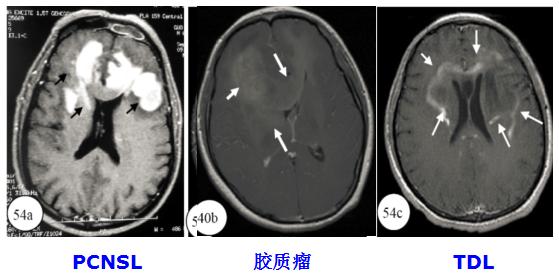

5. TDL与胶质瘤、PCNSL的影像对比

图 环形病灶

3. CT影像鉴别

(1)CT高密度可基本除外TDL。

(2)PCNSL的高密度征(83.3%)较胶质瘤(60%)更为常见。

(3)高密度的形态:点片状、均匀片状、环状及弥漫高密度。

(4)CT高密度可能与核浆比例高相关,与肿瘤级别无关。

(1)TDLs的MRI-T2WI往往边界清楚,胶质瘤的MRI-T2WI边界相对模糊。